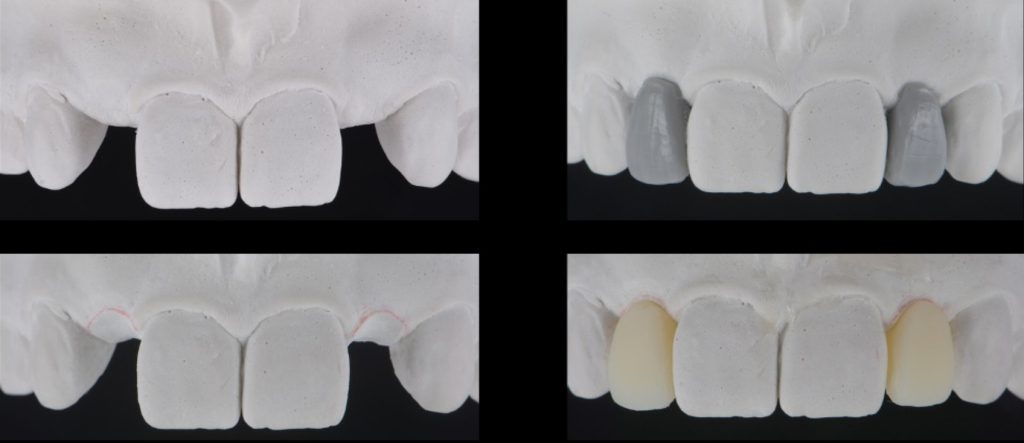

Solution #2: Resin-Bonded Fixed Dental Prostheses (RBFDP)

RBFDP is a proven solution for congenitally missing lateral incisors (Figs. 2-12). Although it is considered an interim restoration, the literature provides substantial evidence supporting its long-term potential. However, the clinical performance of an RBFDP is significantly superior to that of a bilateral retainer, and the dissimilar mobility of the abutment teeth explains this.

Space requirements and connector dimensions depend on material selection. Utilizing zirconia has been proven to be more predictable over time, and recommended connector dimensions are:

- 3.0 mm in height

- 2.0 mm in width

- The retainer wing thickness is 0.7 mm

The amount of tooth reduction is based on available interocclusal space, and often, there is enough space requiring minimal preparation. The key is to stay in enamel. It is also advisable to stay 2.0 mm away from the incisal edge so that the zirconia retainer does not affect the translucency of the natural tooth.